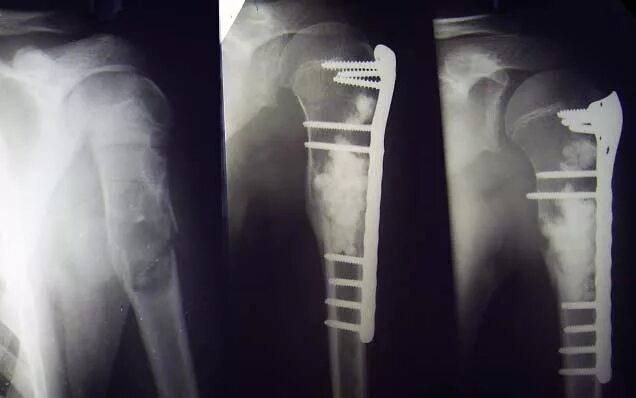

Патологический перелом бедра